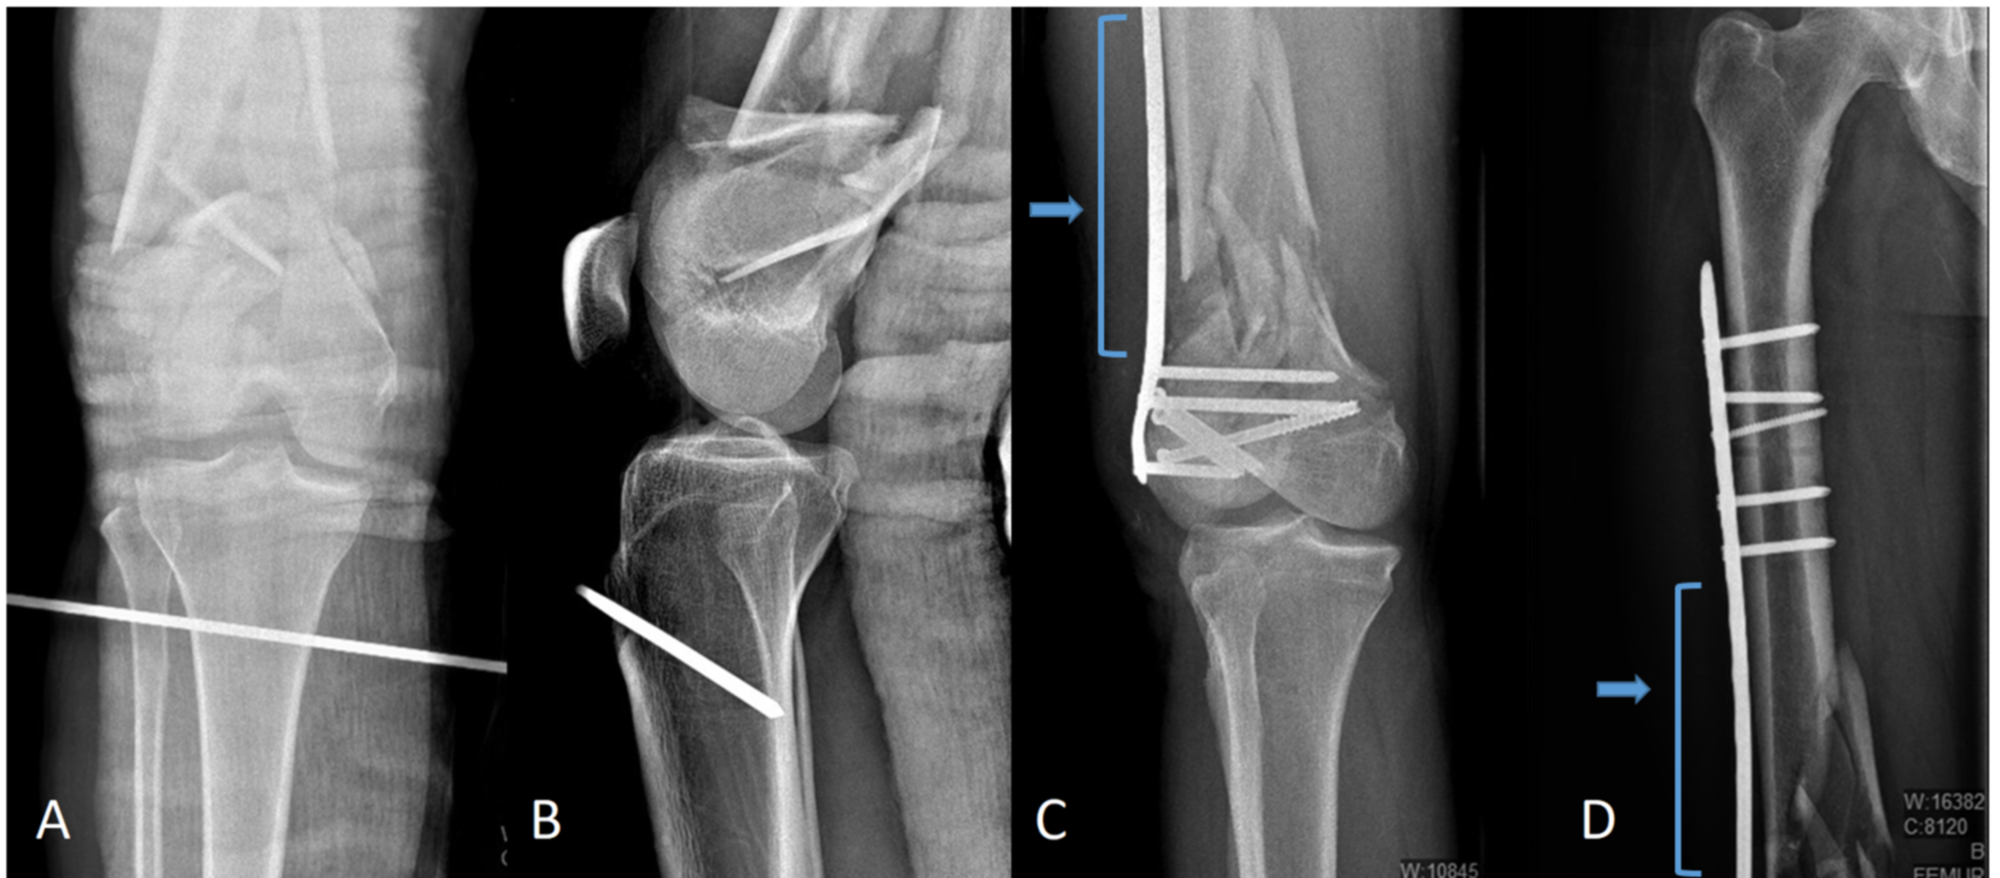

Case 15, type IIc floating knee with (A) closed fractures of the left Floating Knee Radiology in 1975, blake and mcbryde 1 established the concept of the ’floating knee’ to describe homolateral fractures of the. The combined ipsilateral fractures of both the femoral. floating knee refers to the knee joint and not necessarily the connection to either long bone. floating knee is used to describe fractures of the ipsilateral femur and tibia. . Floating Knee Radiology.